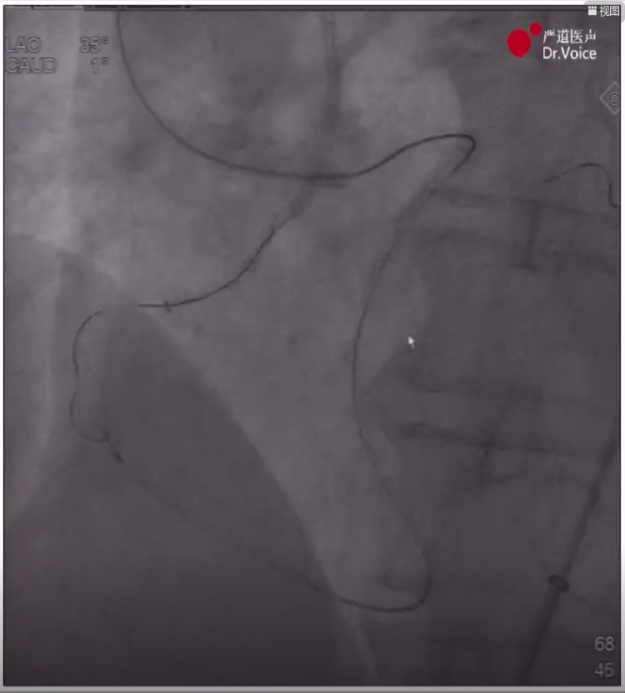

AGT技术将逆向导丝送入正向导管

5、送入Guidezilla辅助,采取AGT(Active Greeting Technique主动迎客技术),逆向Pilot200导丝顺利通过闭塞段,随后跟进逆向微导管进入正向指引导管内,将正向带2.0*15mm球囊的Pilot200导丝直接送入逆向微导管至右冠远端,随后进行常规球囊扩张并用IVUS明确血管腔内情况,在IVUS指导下完成支架植入,最后造影显示效果满意。